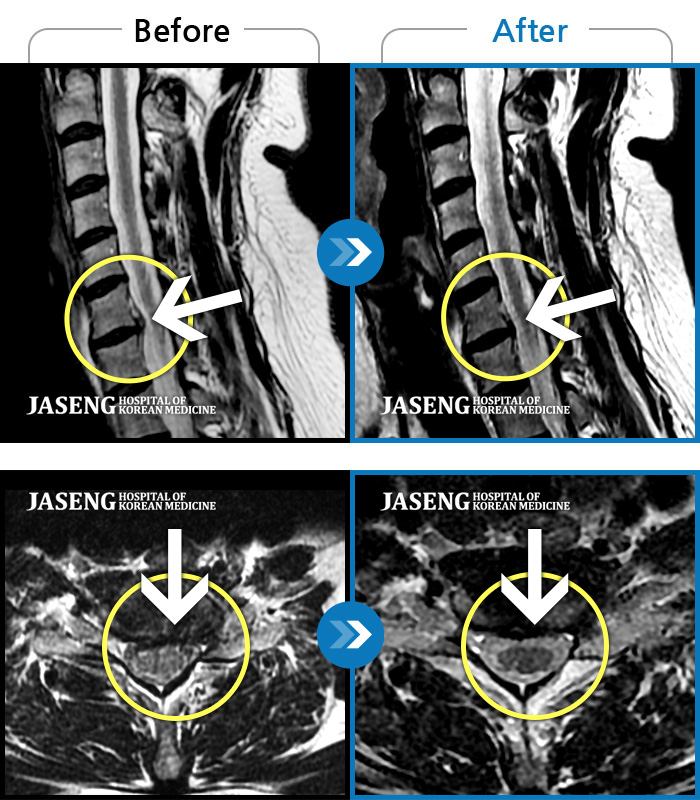

MRI ũ ʸ Ȯϼ.